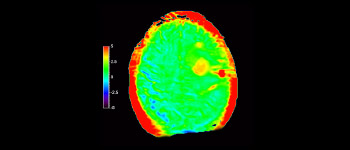

In a society where neurological disorders represent a heavy burden, Philips is committed to provide superb diagnostic clarity and treatment guidance for all patients. Today, although MR is the gold standard in neuro oncology imaging, its accuracy in tumor grading and treatment follow up assessment can be further improved. 3D APT (Amide Proton Transfer) is a unique, contrast-free, brain MR imaging method addressing the need for more confident diagnosis in neuro oncology. 3D APT uses the presence of endogenous cellular proteins, to produce an MR signal that directly correlates with cell proliferation, a marker of tumoral activity. 3D APT can support trained medical professionals in differentiating low grade from high grade gliomas and, in differentiating tumor progression from treatment effect1.

Brain with glioblastoma

with 3D APT